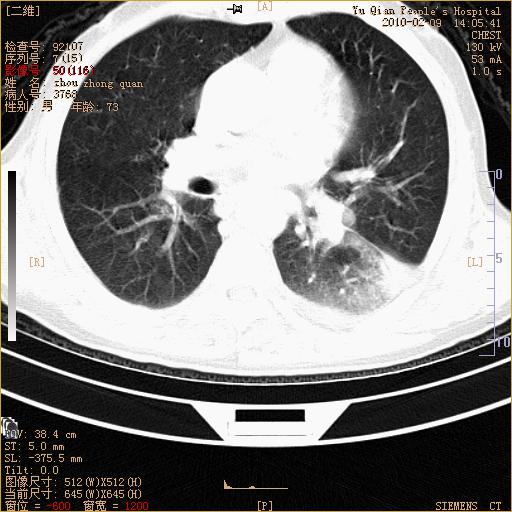

男性,73岁,咳嗽咳血数天,诊为肺ca伴左肺下叶后段阻塞性炎症、肺不张妥否?

右下肺有转移?

左下肺中央型肺癌伴结段形肺不张,左侧胸腔积液,纵隔内见部分增大淋巴结(反应性增生或转移)

左下基底干支气管明显变窄。

左肺下叶基底段支气管狭窄,左肺门增大,左肺下叶团片状病灶。中心型肺癌伴柱塞性炎症可能大,建议支气管镜检查。

左下肺中央型肺癌伴节段性肺不张,左侧胸腔积液,纵隔内见肿大淋巴结

左下基底段支气管变窄。建议进一步纤支镜检查。

1、左肺下叶后基地段肺癌伴阻塞性炎症,左下肺门淋巴结转移。2、左侧胸腔积液。